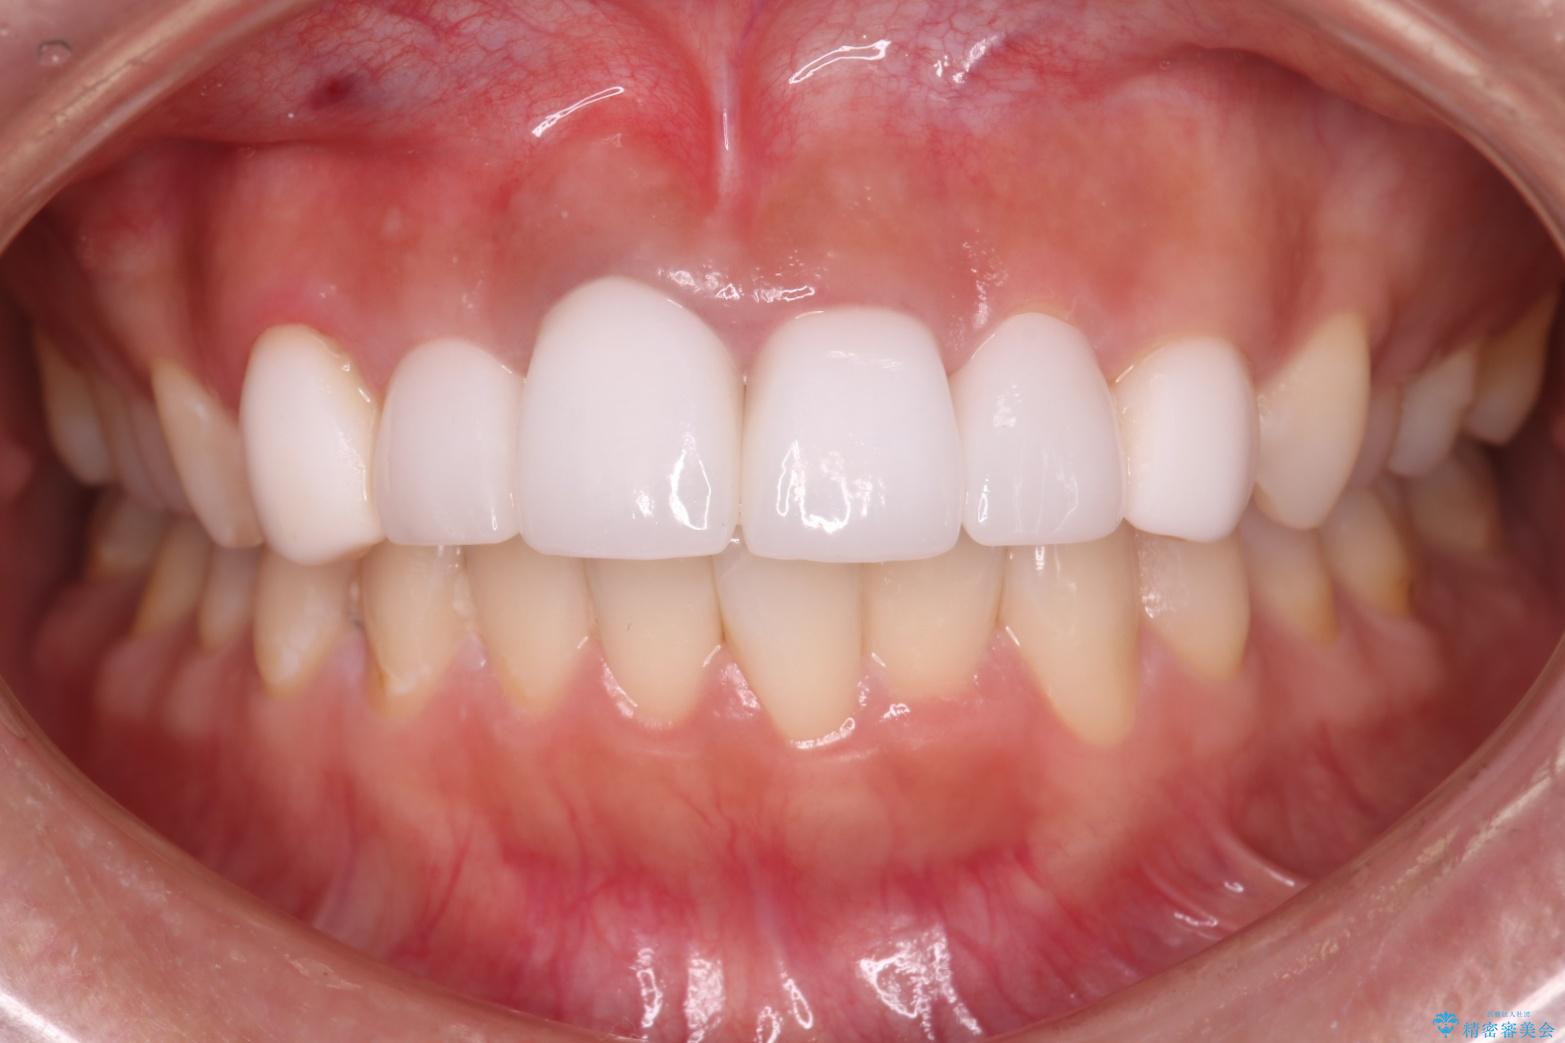

清掃性も上がったおかげで、歯肉の状態も良好に保てています。

色の調和もとれ、患者様には大変ご満足いただけました。